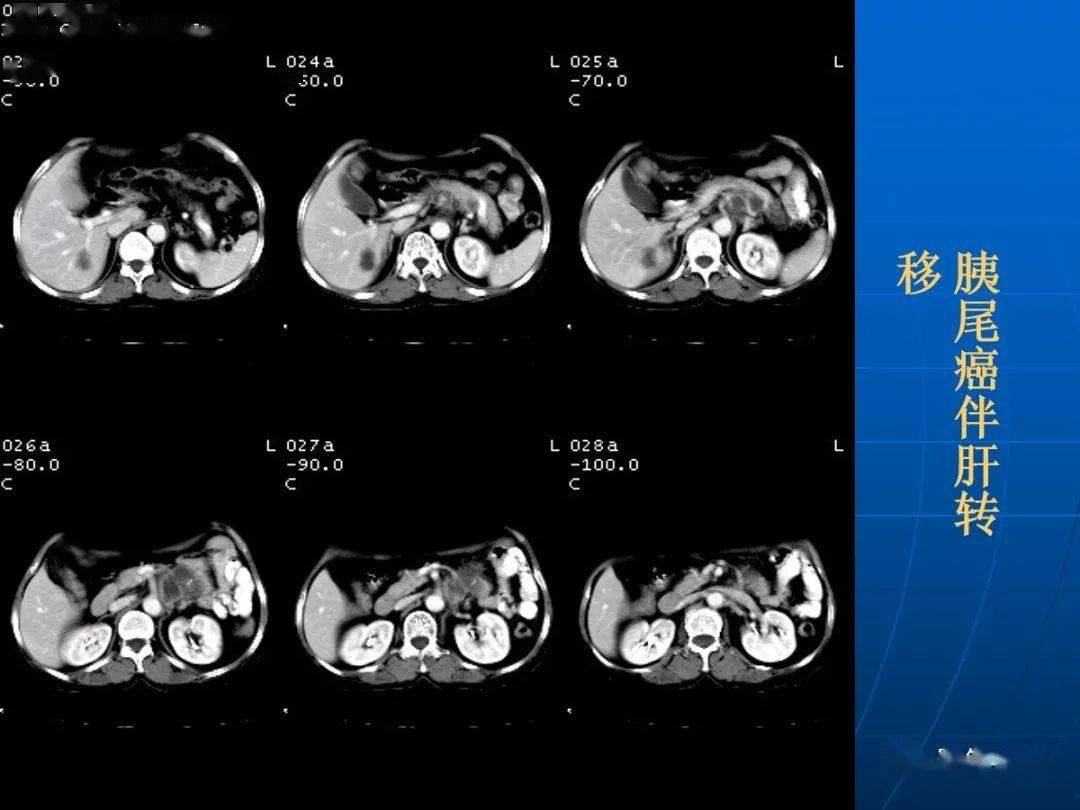

9种胰腺常见疾病的ct诊断